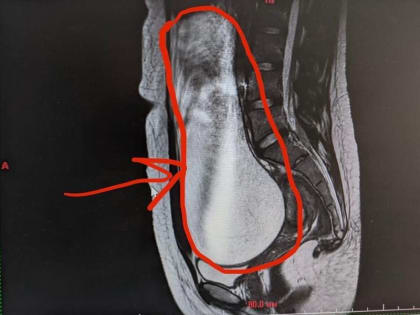

3-литровую кисту удалили воронежские врачи у 15-летней девочки

Уникальную операцию по удалению 3-литровой кисты из брюшной полости 15-летней пациентки успешно провели хирурги Воронежской областной детской клинической больницы №2.

Трёхлитровую кисту удалили врачи 15-летней девочке в Воронеже

Медики из областной детской больницы №2 успешно провели уникальную операцию девочке в Воронеже.

Воронежские хирурги удалили у 15-летней пациентки трехлитровую кисту

Школьницу уже выписали из больницы Текст — Юлия Мостовая, фото — vk.